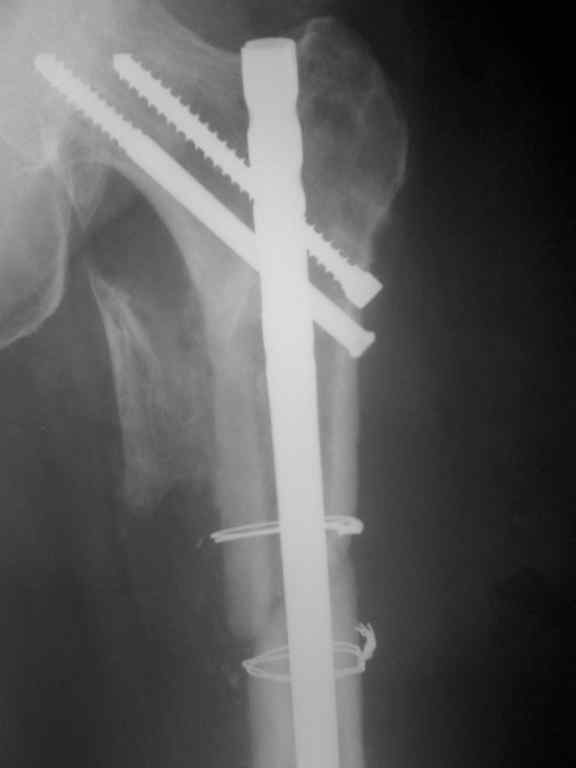

Re: Несросшийся перелом бедра.Выбор операции?

Р-гр после реостеосинтеза